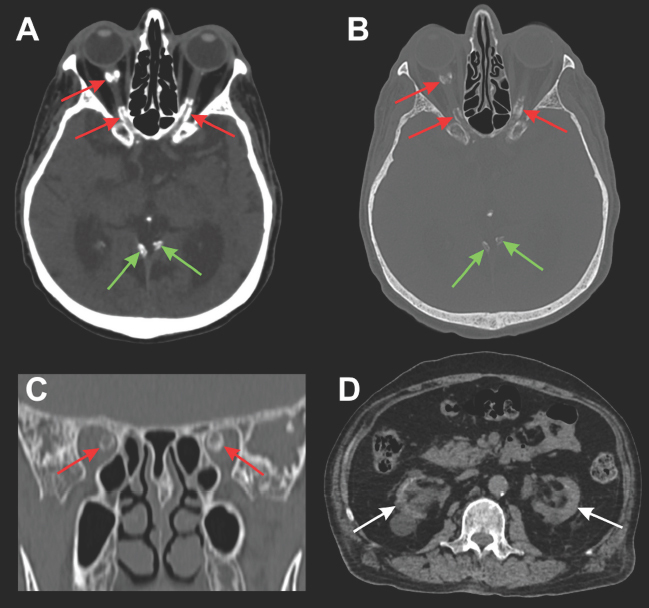

Optic nerve sheath calcification in a patient with chronic kidney disease: an unusual orbital manifestation.

{"title":"Optic nerve sheath calcification in a patient with chronic kidney disease: an unusual orbital manifestation.","authors":"Lara Hemerly De Mori, Nina Ventura, Diogo Goulart Corrêa","doi":"10.1590/2175-8239-JBN-2025-0085en","DOIUrl":null,"url":null,"abstract":"","PeriodicalId":14724,"journal":{"name":"Jornal brasileiro de nefrologia : 'orgao oficial de Sociedades Brasileira e Latino-Americana de Nefrologia","volume":"47 3","pages":"e20250085"},"PeriodicalIF":1.3000,"publicationDate":"2025-07-01","publicationTypes":"Journal Article","fieldsOfStudy":null,"isOpenAccess":false,"openAccessPdf":"https://www.ncbi.nlm.nih.gov/pmc/articles/PMC12208610/pdf/","citationCount":"0","resultStr":null,"platform":"Semanticscholar","paperid":null,"PeriodicalName":"Jornal brasileiro de nefrologia : 'orgao oficial de Sociedades Brasileira e Latino-Americana de Nefrologia","FirstCategoryId":"1085","ListUrlMain":"https://doi.org/10.1590/2175-8239-JBN-2025-0085en","RegionNum":0,"RegionCategory":null,"ArticlePicture":[],"TitleCN":null,"AbstractTextCN":null,"PMCID":null,"EPubDate":"","PubModel":"","JCR":"Q3","JCRName":"UROLOGY & NEPHROLOGY","Score":null,"Total":0}